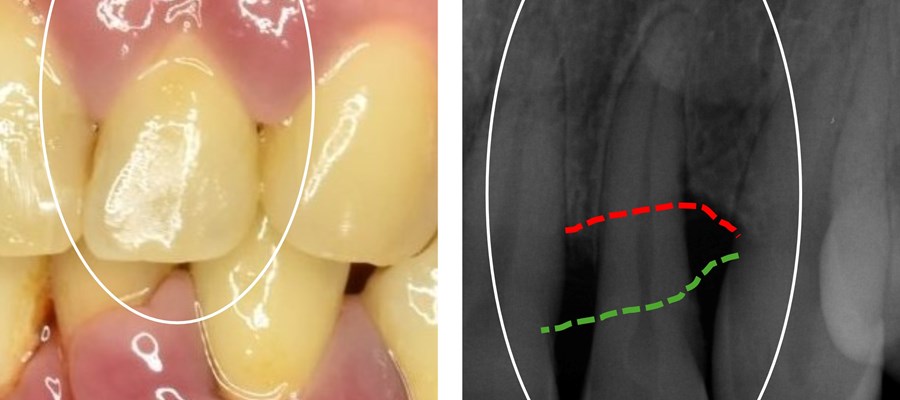

Till vänster en överkäksframtand hos en individ med parodontit. Till höger en röntgenbild av samma tand som avslöjar en markant reduktion av tandens benstöd. Foto: Elin Kindstedt.

Parodontit innebär att en inflammation i tandköttet leder till nedbrytning av de stödjande vävnaderna runt tänderna och kan i svåra fall resultera i tandlossning. Personer med svår parodontit drabbas oftare än andra också av andra allvarliga sjukdomar som hjärtkärlsjukdom och reumatism, men mekanismerna bakom dessa samband är ännu oklara.